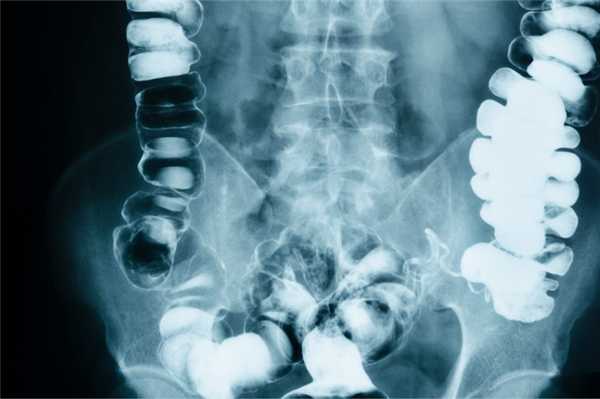

При обзорной рентгенографии брюшной полости определяются характерные кишечные арки (раздутая газом кишка с уровнями жидкости), чаши Клойбера (куполообразные просветления над горизонтальным уровнем жидкости), симптом перистости (наличие поперечной исчерченности кишки). Рентгеноконтрастное исследование ЖКТ применяется в затруднительных диагностических случаях. В зависимости от уровня кишечной непроходимости может использоваться рентгенография пассажа бария по кишечнику или ирригоскопия. Колоноскопия позволяет осмотреть дистальные отделы толстого кишечника, выявить причину обтурации кишки и в ряде случаев - разрешить явления острой кишечной непроходимости.

КТ ОБП C+. Резкое расширение петель подвздошной кишки (красная стрелка) вследствие резкого сужения просвета слепой кишки опухолью (синяя стрелка).

На сегодняшний день разработано множество методов диагностики непроходимости кишечника. Наиболее простыми и доступными из них являются различные рентгенологические методики. При подозрении на обтурационную кишечную непроходимость проводится обзорная рентгенография органов брюшной полости, на которой могут быть видны чаши Клойбера, горизонтальные уровни жидкости и арки воздуха. Эти рентгенологические признаки могут появиться в течение нескольких часов от начала заболевания. При необходимости может быть проведена прицельная рентгенография желудка и ДПК (при подозрении на инородное тело, желчные камни в начальных отделах кишки, аберрантную брыжеечную артерию), снимки в горизонтальной и латеропозиции, на правом или левом боку.

Если явных признаков непроходимости выявлено не будет, рекомендуется провести рентгенологическое исследование с использованием контраста (рентгенографию пассажа бария по тонкому кишечнику, ирригографию). Контрастирование обычно позволяет точно установить локализацию и уровень непроходимости кишечника.